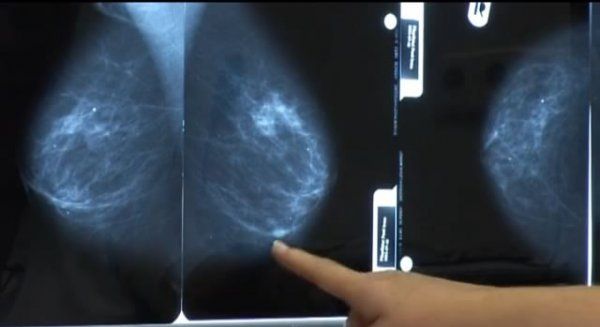

Hosszú évek munkájának eredményeként a megyében harmadikként népegészségügyi emlőszűrést végző szűrőhellyé nyilvánították a halasi kórházat. Így májustól a térségben lakó hölgyeknek nem kell Kecskemétre, vagy Bajára utazni mammográfiára. Halason eddig orvosi beutalóval vizsgálták a nőket, de most már ide vannak irányítva a kétévente felajánlott népegészségügyi szűrésre is.